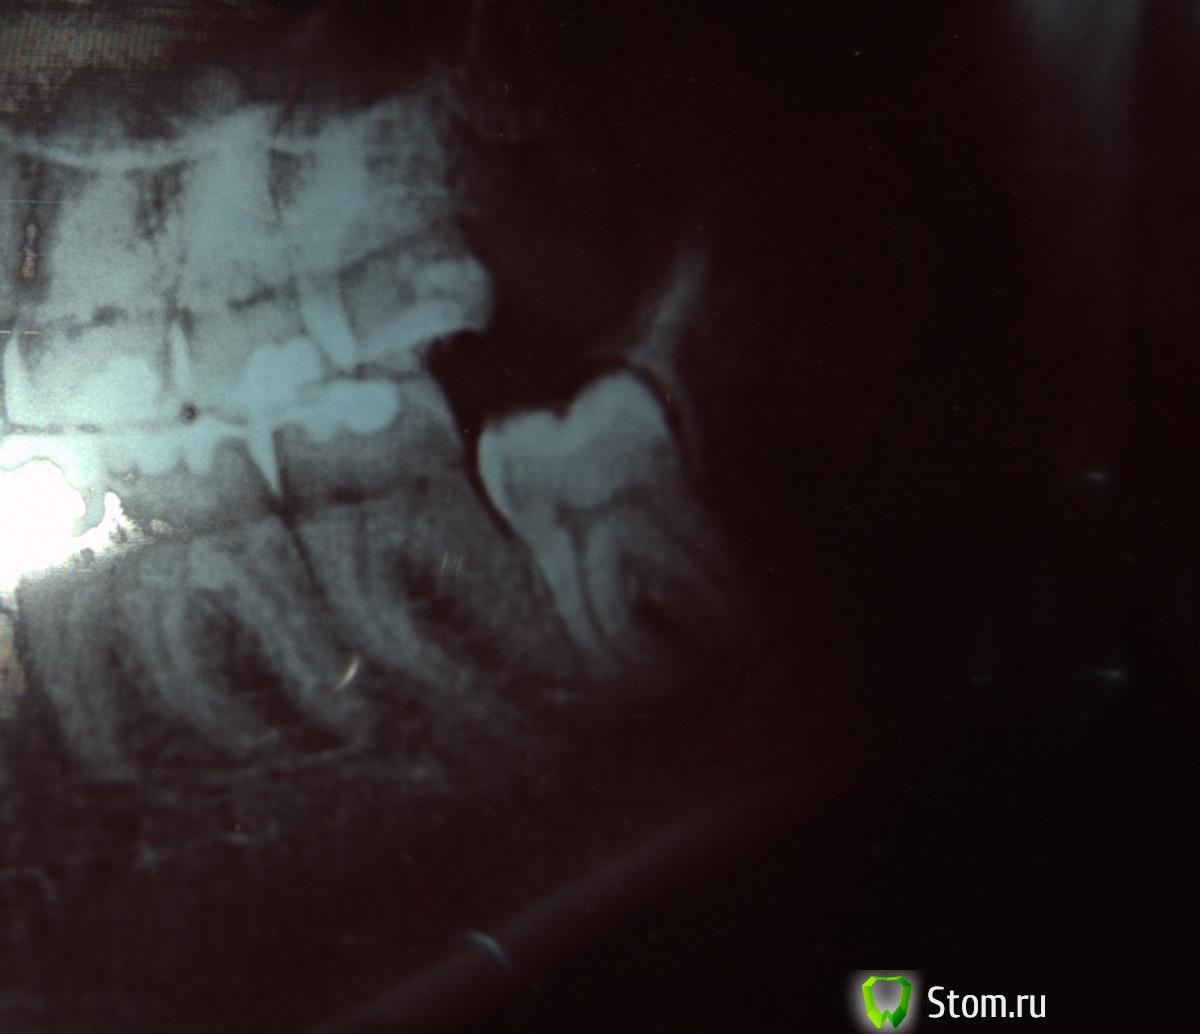

Zverushka Опубликовано 6 марта, 2012 Поделиться Опубликовано 6 марта, 2012 Добрый день. У меня из-за растущей восьмерки стал сильно скучиваться зубной ряд. Пошла к хирургу.Сделали снимок, врач сказал, что чтобы дальше не съезжались, надо удалять восьмерку невыросшую. После удаления стала разглядывать снимок.На мой взгляд явно видна трещина соседней семерки. Но ведь в таком случае удалят надо было не восьмерку, а семерку как я понимаю. То есть я теперь за просто так без двух зубов останусь .Но врач ведь смотрел на снимок, это ведь первое, о чем он должен был бы подумать?Или там не трещина все же? Ссылка на комментарий

kriokov Опубликовано 6 марта, 2012 Поделиться Опубликовано 6 марта, 2012 по такому снимку трещину в 7 не определищь, 8 удален по показаниям (правильно) ИМХО Ссылка на комментарий

Zverushka Опубликовано 6 марта, 2012 Автор Поделиться Опубликовано 6 марта, 2012 А вот та полосочка кривая это не трещина? Которая идет от между корнями и по диагонали вправо? Если так, то я буду очень очень рада . Ссылка на комментарий

Afffinity Опубликовано 6 марта, 2012 Поделиться Опубликовано 6 марта, 2012 Это промежуток между зубами Ссылка на комментарий

x3m Опубликовано 6 марта, 2012 Поделиться Опубликовано 6 марта, 2012 по снимку все ок, 7 не треснувшая.не беспокойтесь Ссылка на комментарий